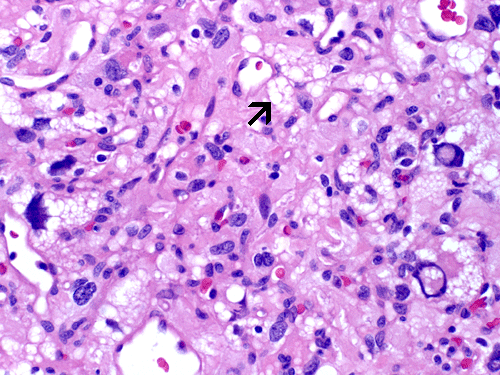

The mass consists of a mixture of spindle cells and clear cells. There is a rich vascular network (Panel A) with sinsusoidal dilatation but no anastomosis of the vascular channels. The endothelial cells appear lean and not protruding into the vascular channel. The clear cells appear to have foamy cytoplasm (̃ in Panel B). The nuclei are hyperchromatic and may appear slighly grooved or lobuated. On immunohistochemistry, the foamy cells are strongly reactive for inhibin (Panel C). These cells are also reactive for S100 protein (Panel D) and neural specific enolase (Panel E) . No immunoreactivity for epithelial membrane antigen (EMA) is observed (Panel F). The tumor is not immunoreactive for cytokeratin.

Microscopically, hemangioblastomas consist of foamy to clear stromal cells interspersed with endothelium lined vascular channels. Clear vacuoles within the stromal cells can be stained with Oil red-O or similar stain if applied to frozen sections. The stromal cells stain strongly for epidermal growth factor receptor (EGFR) and platelet-derived growth receptor factor alpha (PDGF-alpha) 12 and inhibin 13. The stromal cells are typically negative for epithelial membrane antigen (EMA) and cytokeratin 14. In a small number of cases, the stromal cells express glial fibrillary acidic protein (GFAP) 7, 14 and S100 protein 14. These staining results should be interpreted with case as they may represent entrapped glial cells. The admixed capillaries will stain for with typical endothelial markers (Factor-VIII and others) 15, but the stromal cells are typically negative for the endothelial markers. To this date, the pathogenesis and cell origin of hemangioblastomas is not certain.